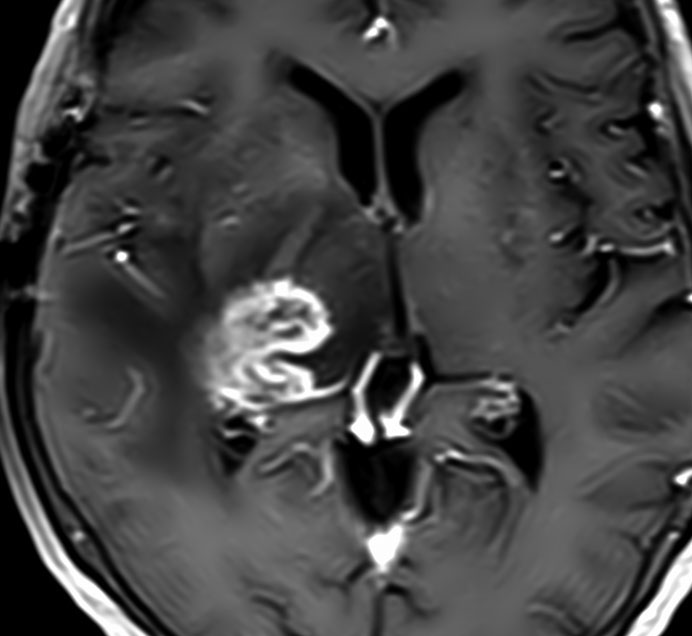

下の病理写真は,ある患者さんから私に送られたものです。20代で前頭葉の膠芽腫になってから21年経って生存しておられるということです。2度の開頭術と放射線治療と化学療法(複数回)を受けておられます。患者さんに病理診断が間違っているのではないかと返事をしたら,下にある画像を送ってくださいました。病理診断は,一見したところは多形膠芽腫 グリブラに間違いありませんでした。でも,ーーー

(下の画像は患者さんの許可を得て掲載させていただきました)

bizarre! 異様な細胞が混在しています。核多型が目立ち,多核巨細胞も混じる典型的な膠芽腫の像です。下の左の画像は血管内皮の肥厚 endovascular proliferationがあり,下の右のKi-67染色では核濃染像が多く核分裂能が高いことを示します。しかし,——

左のGFAP染色では一部の細胞が染色されません,右のHE染色では豊富な血管増殖の間に空砲 perinuclear halo を有した細胞増殖が見られます。さらに,–

腫瘍の部分像として明らかに乏突起膠腫が混在しています。また,どの部分をみても壊死 necrosisがありませんでした。

従って,当時の診断では,この腫瘍の形態病理診断は,退形成性乏突起星細胞腫 anaplastic oligoastrocytoma WHO grade III となります。2018年時点では,もしiDH変異があったと仮定すると,secondary glioblastoma (IDH-mutated glioblastoma)とされるかもしれません。